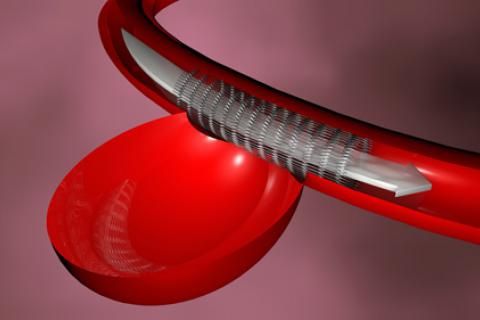

Angioplastia coronaria

Angioplastia coronaria más colocación de stent